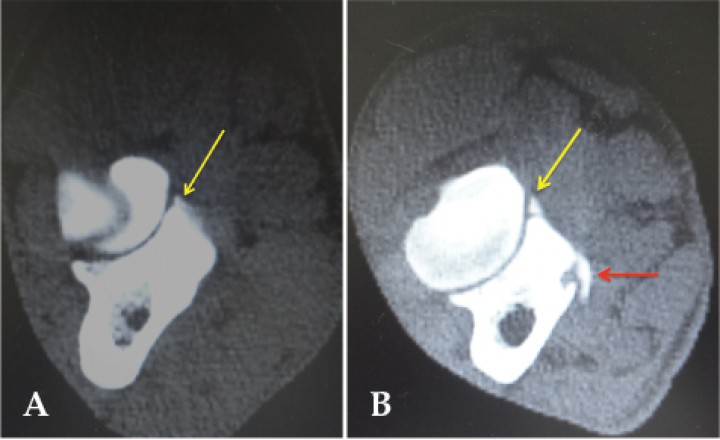

Figura 2

Imágenes de tomografía computarizada en plano transversal y ventana de huesos. (A) Se evidencia un fragmento de coronoides medial (flecha amarilla). (B) Imagen de otro paciente en el que además del fragmento craneal (flecha amarilla), se aprecia la deformidad del coronoides y la presencia de un osteofito en la zona medial del coronoides (flecha roja).